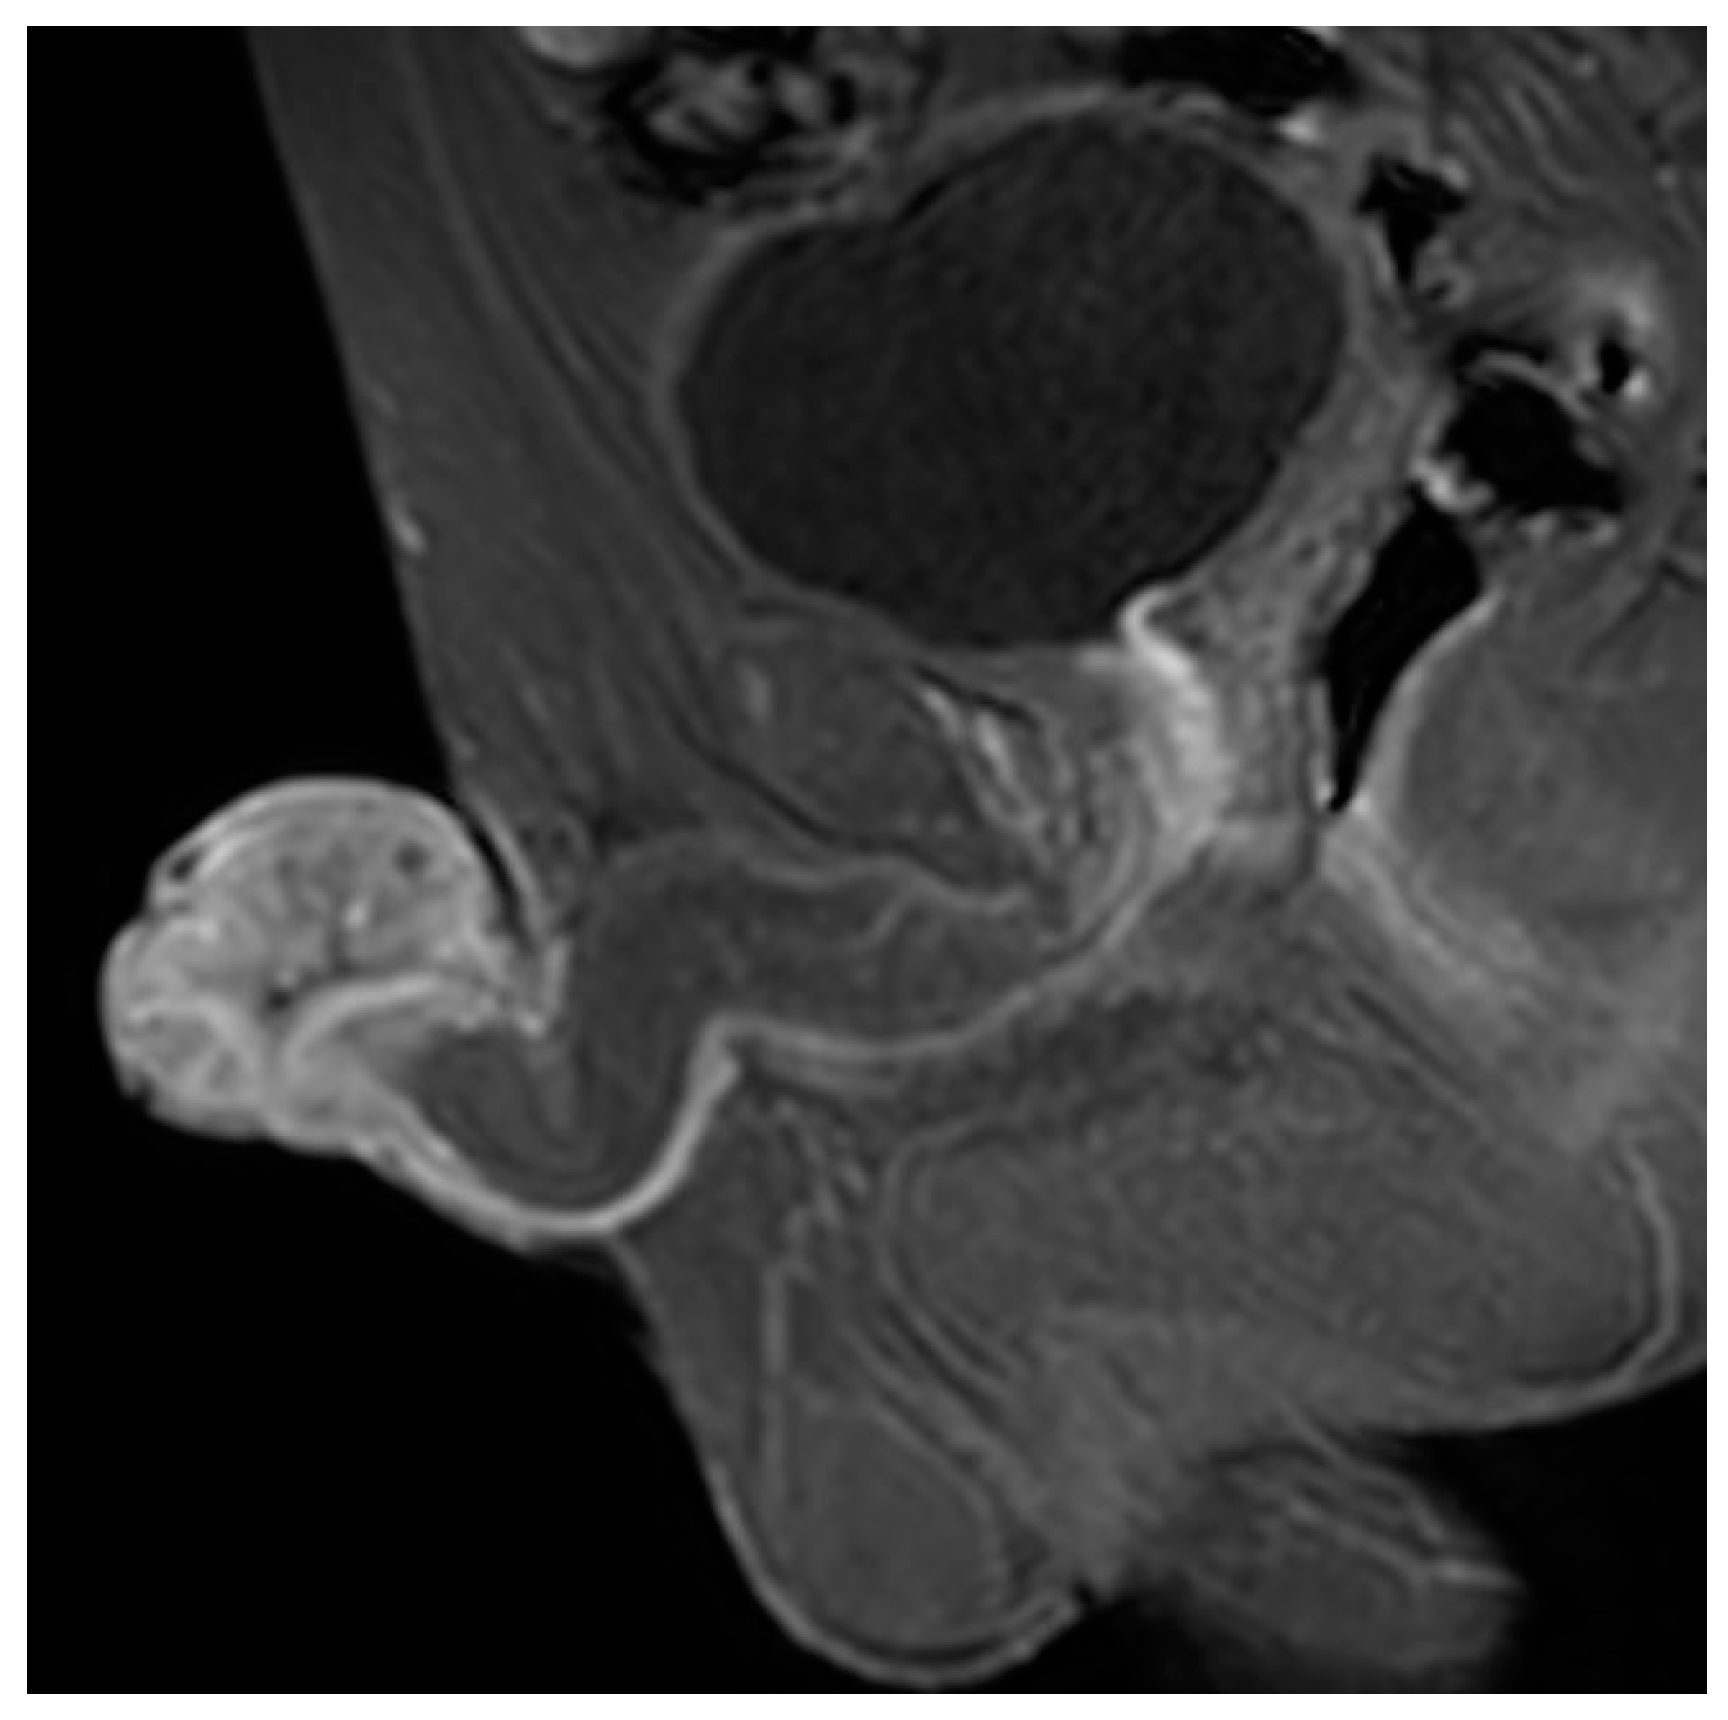

2. Case